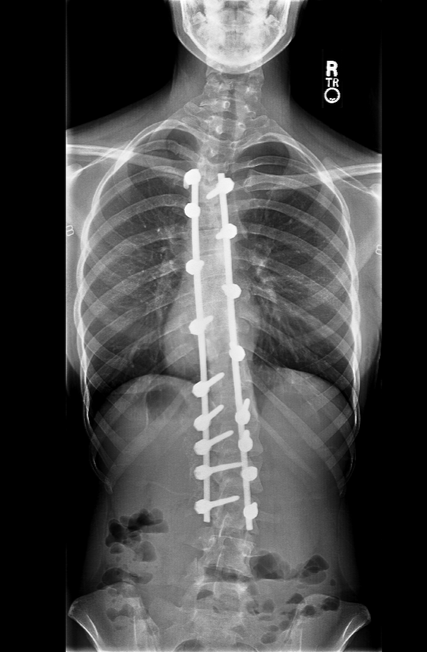

Low Vitamin D Levels Linked to Chronic Low Back Pain

A new study in India suggests the “sunshine vitamin” may also play a role in the development of chronic low back pain.

Researchers at a teaching hospital in eastern India took blood samples from 75 adult patients with chronic low back pain and found a remarkably high rate of low vitamin D serum levels – a condition known as hypovitaminosis D.

While researchers found an association between chronic low back pain and hypovitaminosis D, they did not establish a causal link. Pain severity and disability levels were about equal between the “deficient” and “insufficient” groups, and between men and women.